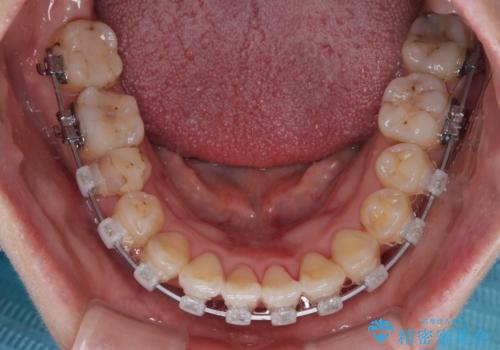

- 矯正装置

- クリアブラケット

- 1年5ヶ月

急速拡大装置により上顎骨幅を側方に拡大し、それを利用して八重歯を歯列に納めることにしました。

急速拡大が奏効し、非抜歯矯正にて八重歯を解決することができました。